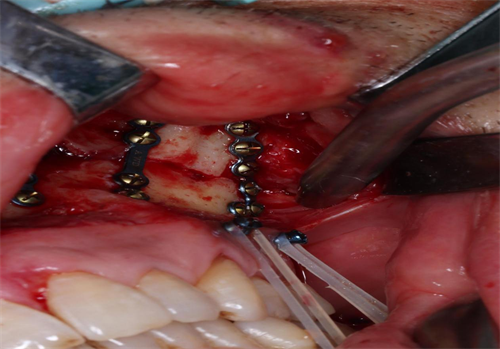

完善术前检查后,口腔科团队依据术前规划设计的方案,在导板的精确序列引导下,为患者实施了“双侧上颌骨及颧骨、右侧颧弓及鼻骨骨折切开复位内固定术、骨折颌间固定术、咬合重建术”。术后,患者骨折断端复位固定效果可靠,咬合关系恢复良好,面部基本对称,手术成效较为理想。

术中骨折断端精确复位